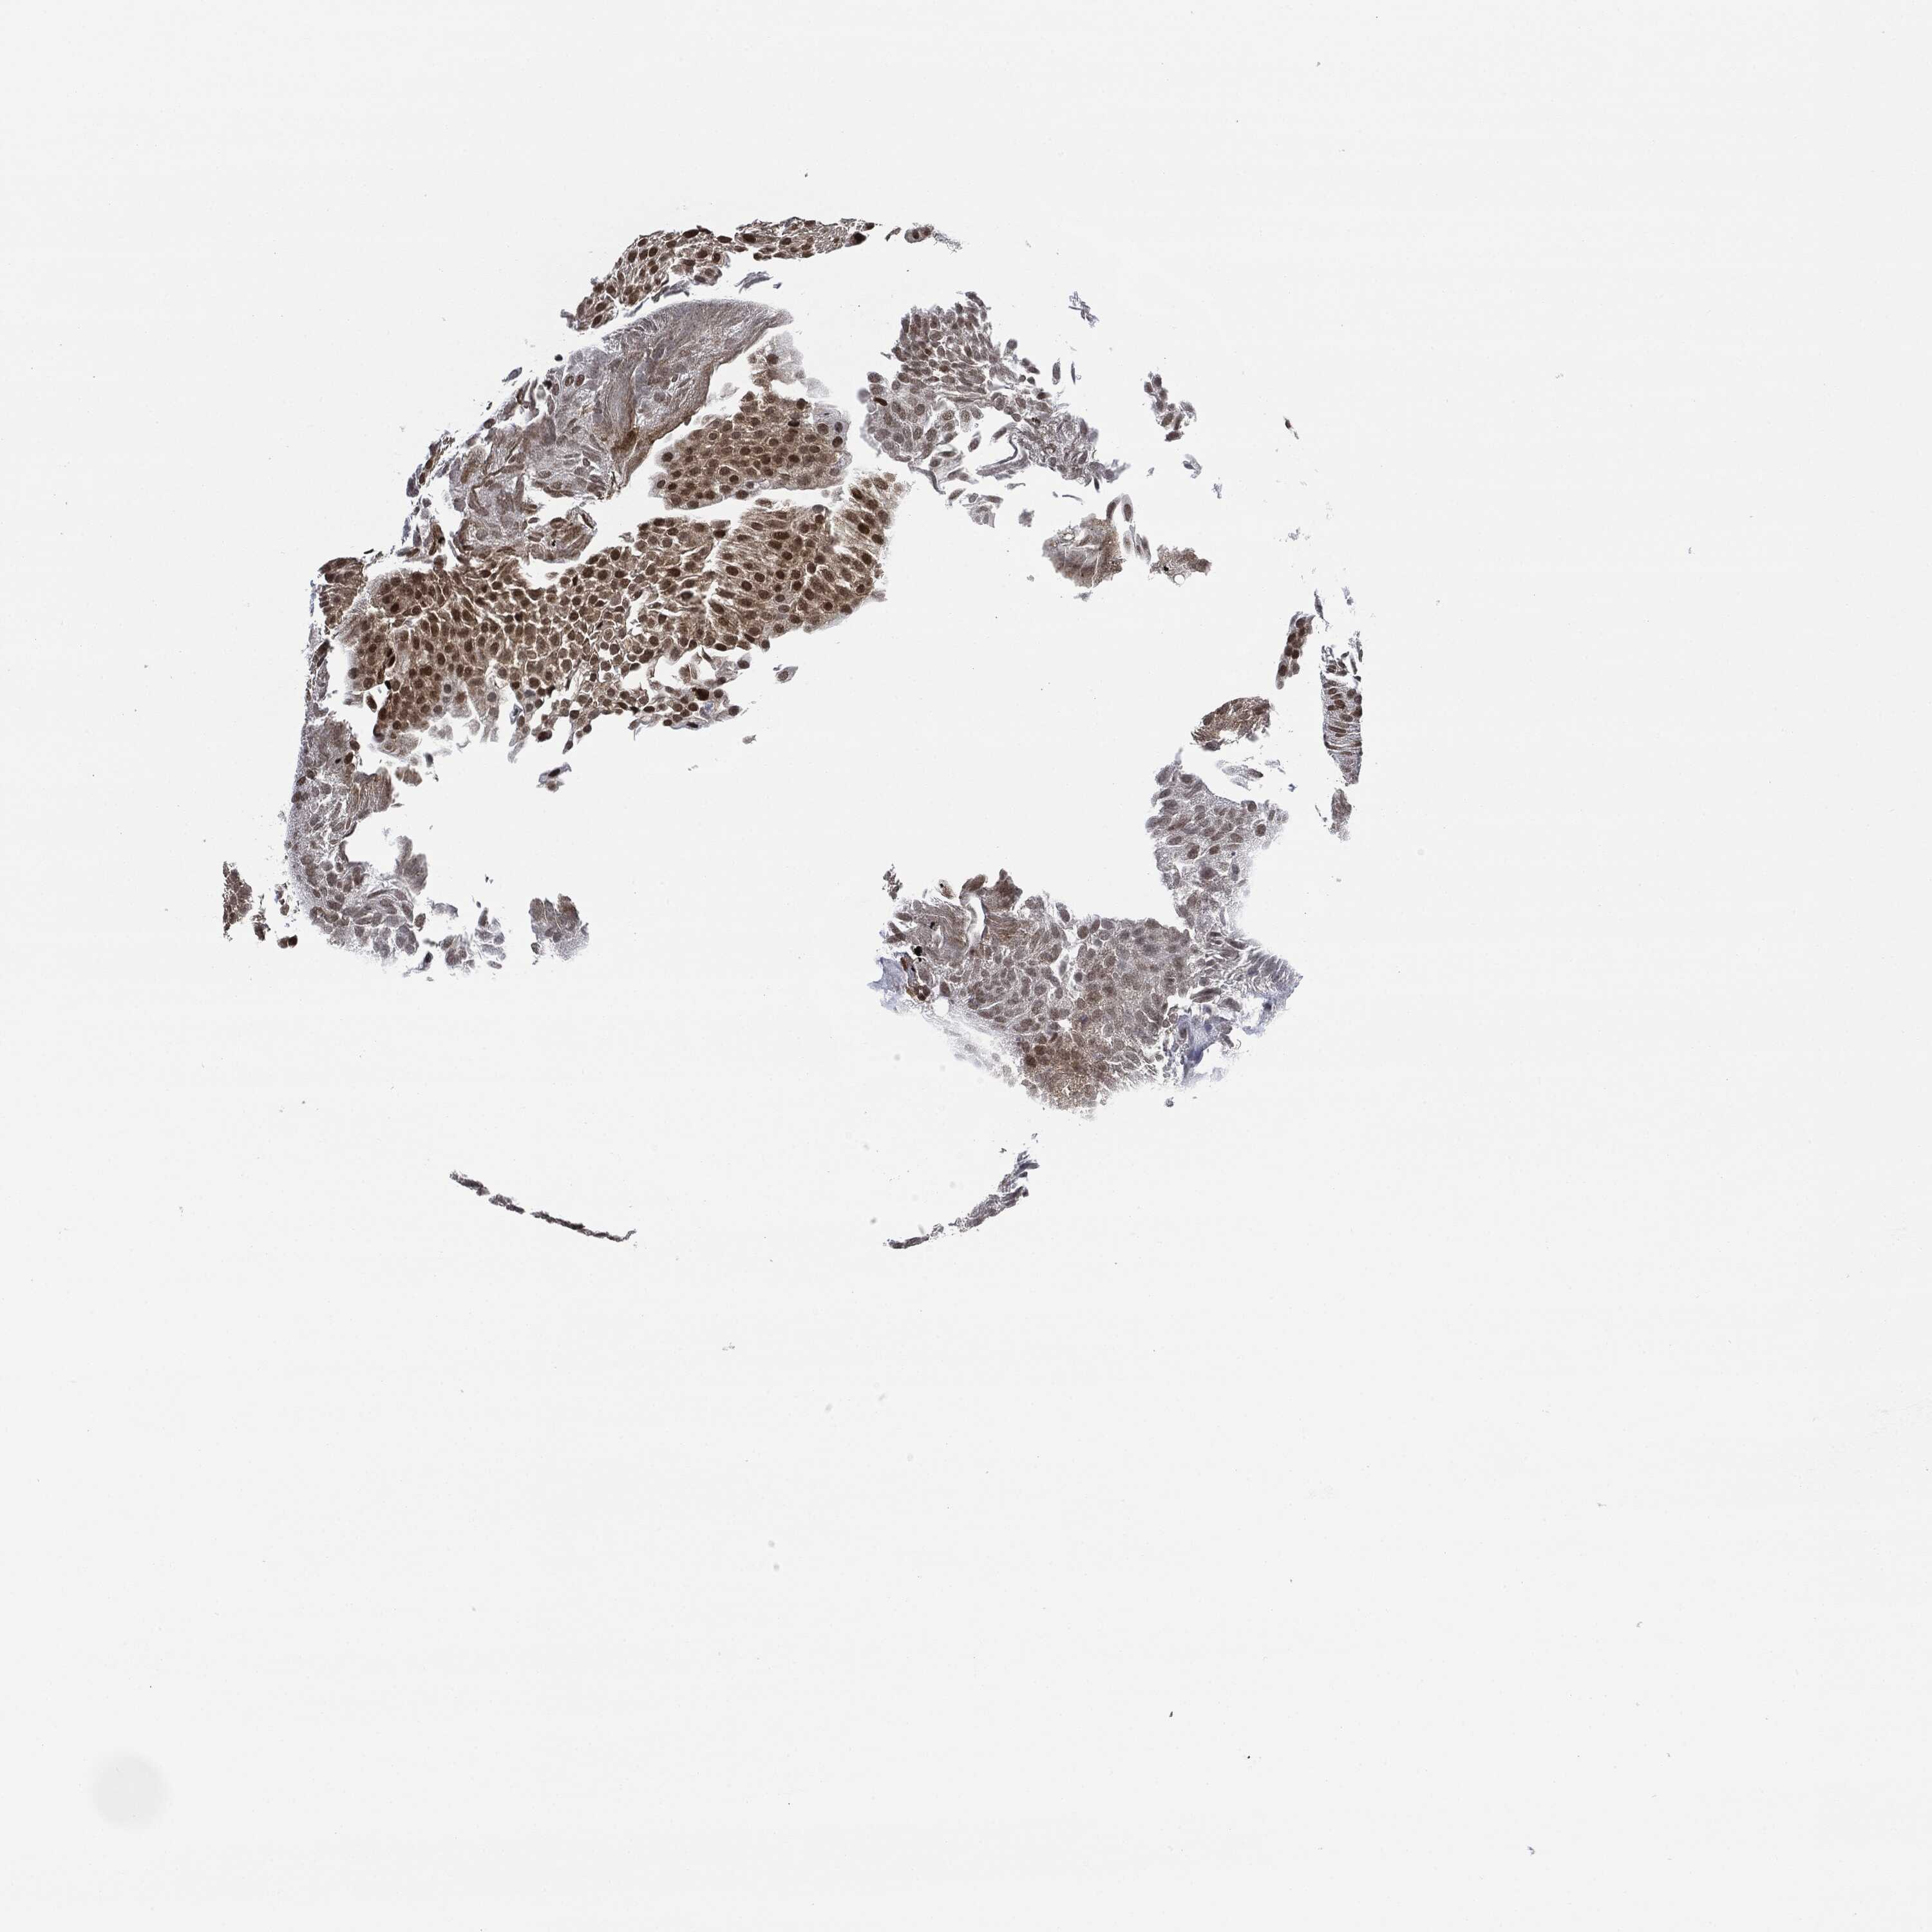

UROTHELIAL CANCER - Protein expressioni

A mouse-over function shows sample information and annotation data. Click on an image to view it in a full screen mode. Samples can be filtered based on level of antibody staining by selecting one or several of the following categories: high, medium, low and not detected. The assay and annotation is described here.

Note that samples used for immunohistochemistry by the Human Protein Atlas do not correspond to samples in the TCGA dataset.

Antibody stainingi

Antibody staining in the annotated cell types in the current human tissue is reported as not detected, low, medium, or high, based on conventional immunohistochemistry profiling in selected tissues. This score is based on the combination of the staining intensity and fraction of stained cells.

Each image is clickable and will lead to virtual microscopy that enables deeper exploration of all samples and also displays staining intensity scores, fraction scores and subcellular localization as well as patient and tissue information for each sample.

HPA001252

Urothelial carcinoma, High grade

Urothelial carcinoma, Low grade

Adenocarcinoma, NOS